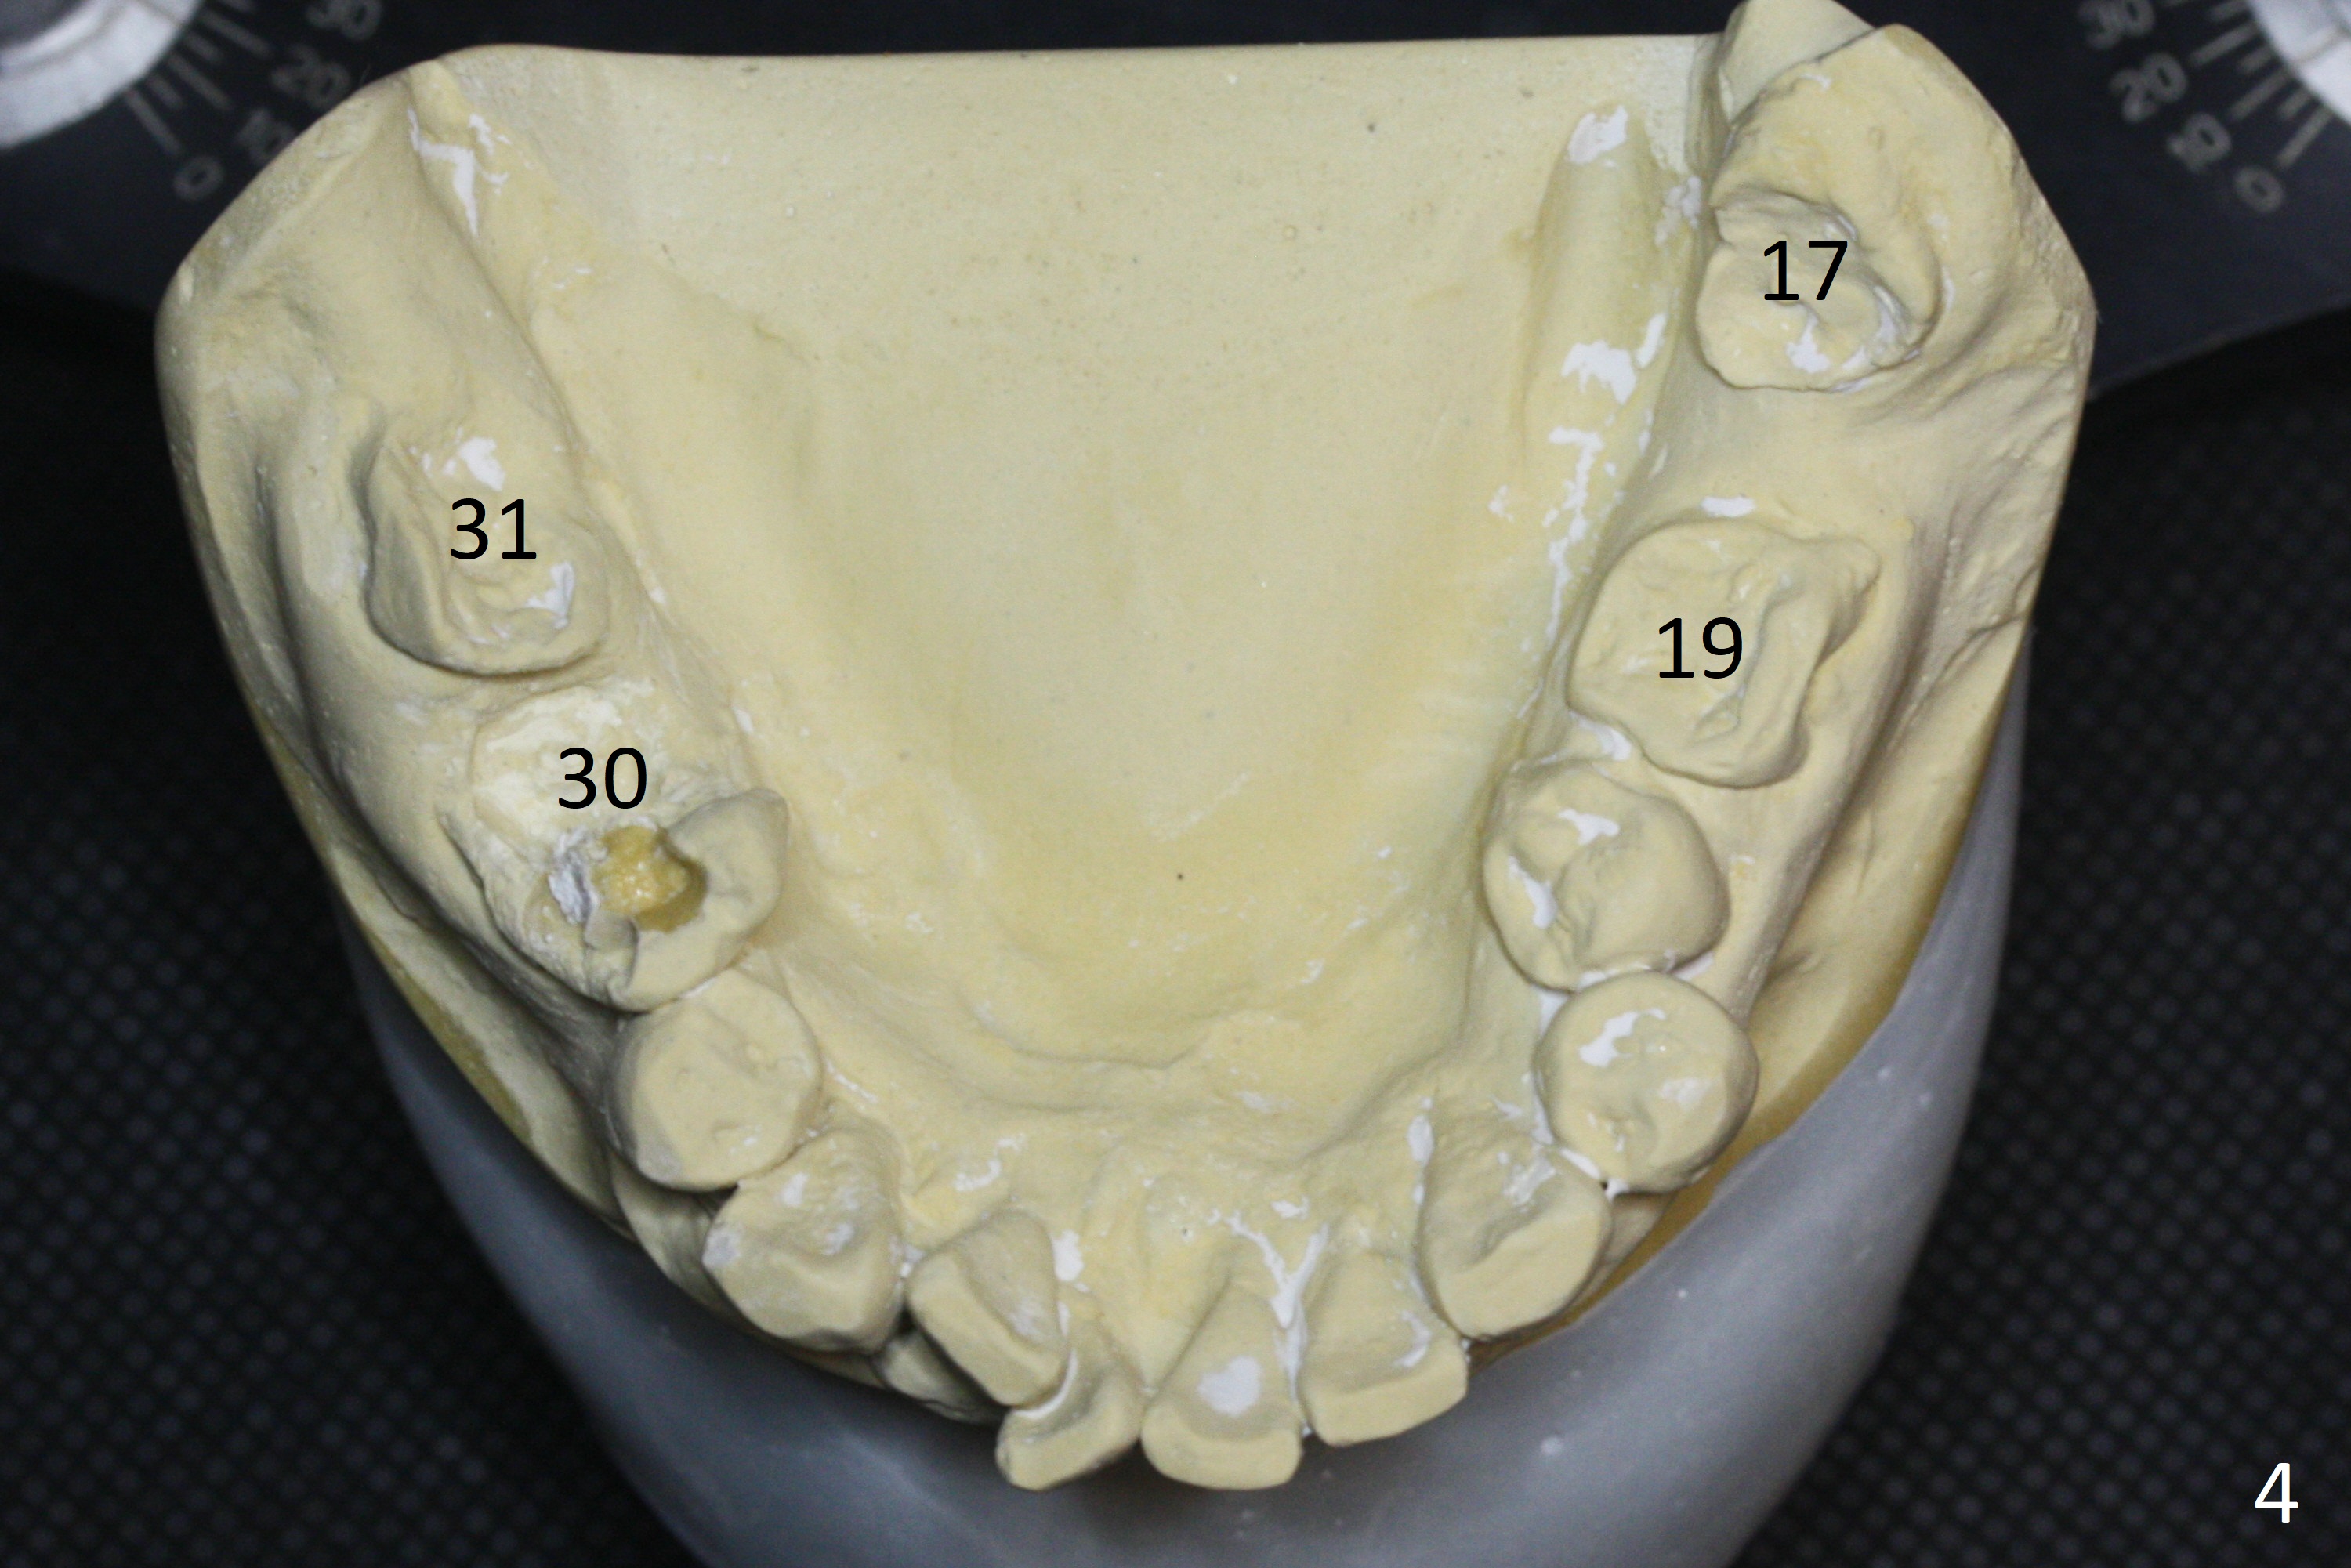

A 54-year-old man is 5 years post liver cancer surgery. After his platelet count returns normal, he wants to take care of his teeth. Most of his molars (#14, 19, 30,31) need extraction and implant placement (Fig.1-4). Although the 2nd premolars on the right are missing (Fig.1,3,4), it seems appropriate to establish 2 molar occlusion on the right (Fig.5,7,8) and 1 on the left (Fig.6,7 (because of #15 supraeruption (Fig.2 arrow))) . Since the residual roots in the lower right quadrant are irritating, implant placement will be done first (Fig.11, Clindamycin), followed by #2,3 (Fig.10) and 14(Fig.12 IBS) and 19 (Fig.12). Use IS drills and 4 and 5 mm stoppers to start osteotomy at #30 and 31, respectively.